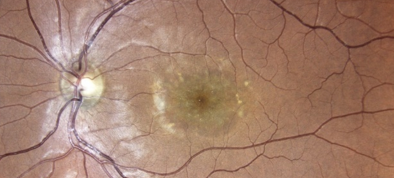

Farbfundusfotos eines Patienten mit Makuladystrophie.